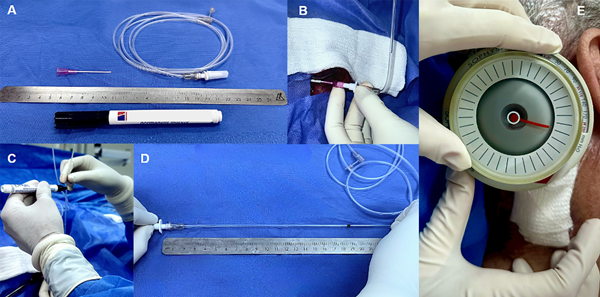

Protocolo quirúrgico

En la segunda parte del trabajo, basándonos en los resultados de nuestro estudio retrospectivo, desarrollamos un sencillo y económico protocolo intraquirúrgico a fin de evaluar la presión de LCR de cada paciente e individualizar la presión óptima del sistema valvular a implantar. Los materiales a utilizar son un catéter abbocath G20, una guía B-Pro 26 o similar, una regla estéril, un marcador estéril y el sistema regulador de la válvula a colocar (Fig. 1A).

Figura 1. Protocolo quirúrgico.

Fig. A. Elementos a utilizar para realizar el protocolo (catéter abbocath G20, guía B-Pro 26 o similar, regla estéril y marcador estéril). Fig. B y C. Punción ventricular y colocación del teflón del catéter abbocath 20G dentro del mismo. Posteriormente este se une con la guía B-Pro 26 y se eleva a fin de evaluar la presión obtenida (medida por la columna de LCR). Fig. D. Medición de la columna de agua marcada en la guía B-Pro 26 con la regla estéril. Fig. E. Finalmente, una vez concluido el procedimiento, se regula la válvula a la presión obtenida intra quirúrgicamente.

El protocolo consiste en 5 sencillos pasos, a realizar dentro del proceso de colocación de la válvula (Fig.1):12